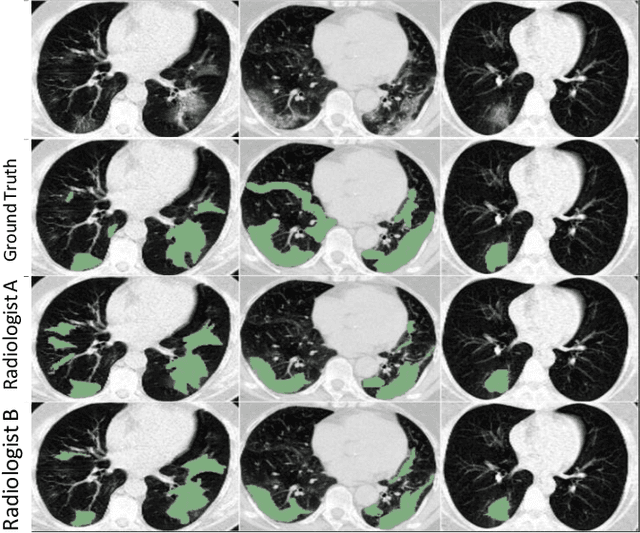

Abstract:Segmentation of infected areas in chest CT volumes is of great significance for further diagnosis and treatment of COVID-19 patients. Due to the complex shapes and varied appearances of lesions, a large number of voxel-level labeled samples are generally required to train a lesion segmentation network, which is a main bottleneck for developing deep learning based medical image segmentation algorithms. In this paper, we propose a weakly-supervised lesion segmentation framework by embedding the Generative Adversarial training process into the Segmentation Network, which is called GASNet. GASNet is optimized to segment the lesion areas of a COVID-19 CT by the segmenter, and to replace the abnormal appearance with a generated normal appearance by the generator, so that the restored CT volumes are indistinguishable from healthy CT volumes by the discriminator. GASNet is supervised by chest CT volumes of many healthy and COVID-19 subjects without voxel-level annotations. Experiments on three public databases show that when using as few as one voxel-level labeled sample, the performance of GASNet is comparable to fully-supervised segmentation algorithms trained on dozens of voxel-level labeled samples.